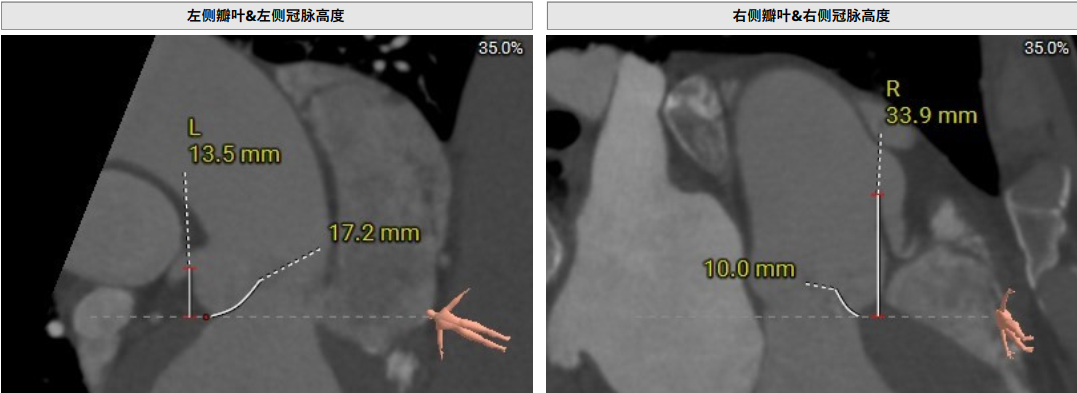

术前CT评估提示,患者主动脉瓣三叶瓣,瓣叶增厚,舒张期右冠瓣脱垂,右冠瓣瓣叶轻度钙化,存在三个瓣窦,分布较均匀;主动脉瓣环周长折算直径28.0mm;左心室流出道周长折算直径29.5mm,无钙化,无狭窄;STJ直径35.3mm,升主动脉直径41.8mm;双侧冠脉开口高度可LCA13.5mm ,瓣叶长17.2mm;RCA33.9mm,瓣叶长10.0mm;侧左冠脉轻度钙化;横位心,左室主动脉夹角为135°;